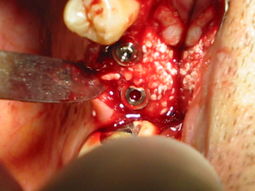

111-1173_IMG.JPG

...la foto mostra il riempimento di un piccolo gap, con associazione di granulato osseo cortico-spongioso eterologo e l'aggiunta di acido polilattico-poliglicolico...